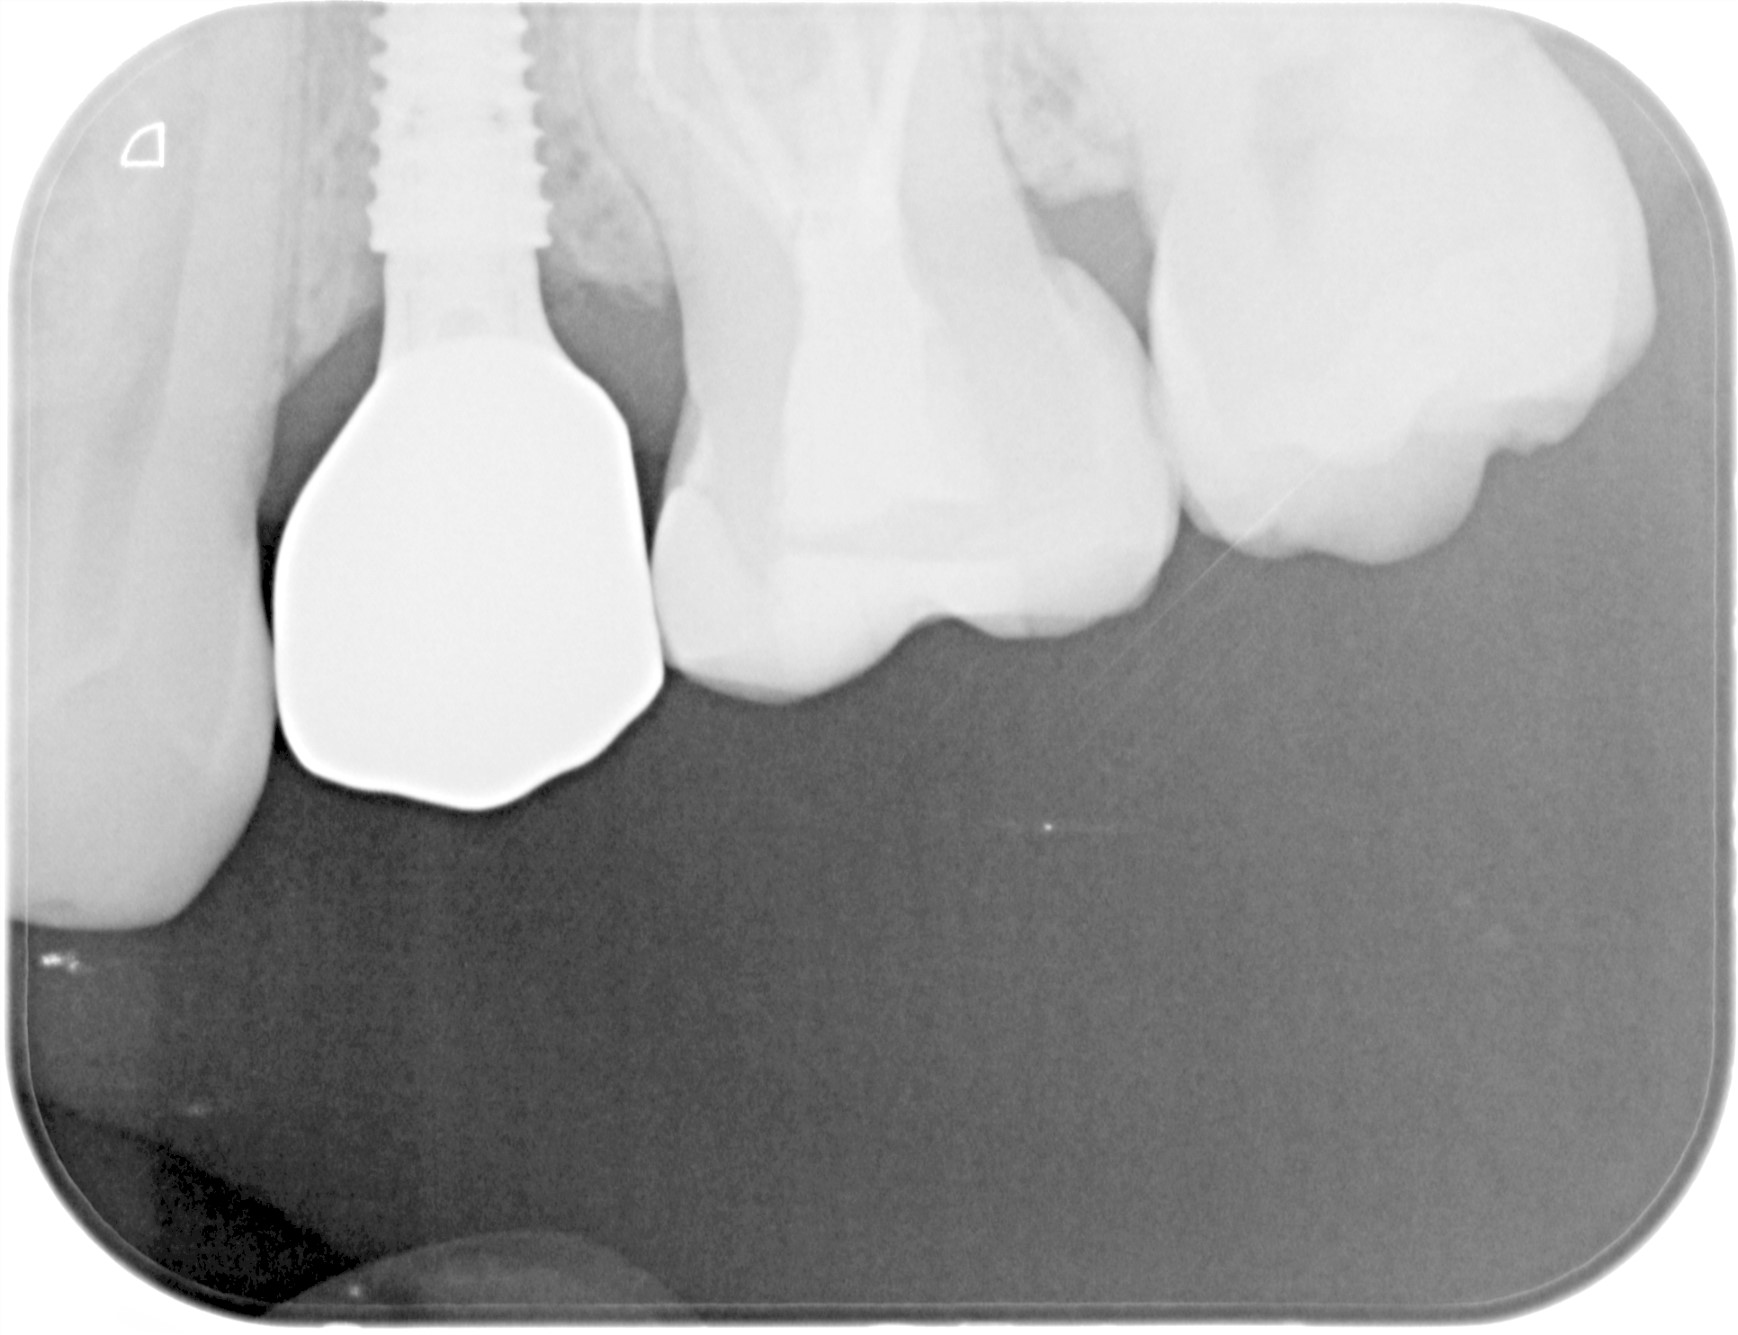

治療後レントゲン写真

- 治療名称

- 右下56番パーシャルデンチャー部のインプラント治療

- 患者の症状

- 60代女性 右下56番にパーシャルデンチャーを装着しており機能及び審美的に問題を抱えている。

- 治療内容

- まず、CT撮影による精密な骨の分析・治療計画を立てガイドを使いインプラント埋入しインプラントが骨と結合するのを待つ間に仮の歯を入れます。その後本歯を作成して装着しました。

- 治療期間・回数

- インプラント埋入からジルコニアセットまで三か月半

- 費用

※自由診療となります - ■総額:¥660,000(税込み) ■内訳:埋入(ガイド込み)¥200,000×2、仮歯¥20,000×2、被せ物¥80,000×2

- リスク・副作用

- ・術後の腫れ・痛み・出血 ・感染(インプラント周囲炎) ・インプラントの脱落 ・神経損傷によるしびれ ・破損・ゆるみ